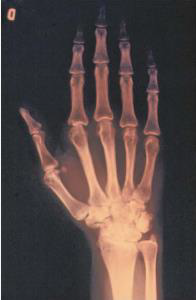

A imagem a seguir representa a radiografia de mão em PA em que se observam osteosteopenia periarticular; redução dos espaços articulares das articulações interfalangianas proximais, das metacarpofalangianas, dos ossos do carpo e da articulação radiocárpica; erosão periarticular na 2ª articulação metacarpofalangiana, cistos ósseos nas 1 ª· 2ª e 4ª articulações metacarpofalangianas.

Fonte: Carvalho (2019)

Baseando-se na análise da imagem, juntamente com a descrição apresentada, o diagnóstico sugestivo é: